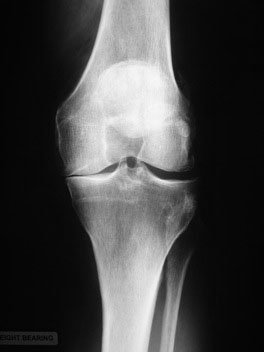

When you stand to have an X-ray taken of your knee, even though you are standing the X-ray will look as though there is thin air between the ends of the bones because the sandwich of the three non-bony structures - the joint surface cartilage on the end of the thigh, on the top of the shin and the meniscus inbetween - does not show up on the X-ray. If this sandwich is reduced by arthritis, the X-ray will reflect this as a loss of the "space" between the bones.

Osteoarthritis of the knee most commonly occurs in the inner (medial) compartment and frequently the rest of the knee remains relatively healthy. This X-ray shows this. To the left of the image you can see that the inner medial side is worn and has no space between the bones. The outer lateral side to the right of the image is normal with the gap taken up by with the 'invisible' joint surface cartilage and shock absorbing meniscal cartilage. (Remember that the lateral side is the side that has the skinny fibula bone next to the fatter tibia bone).